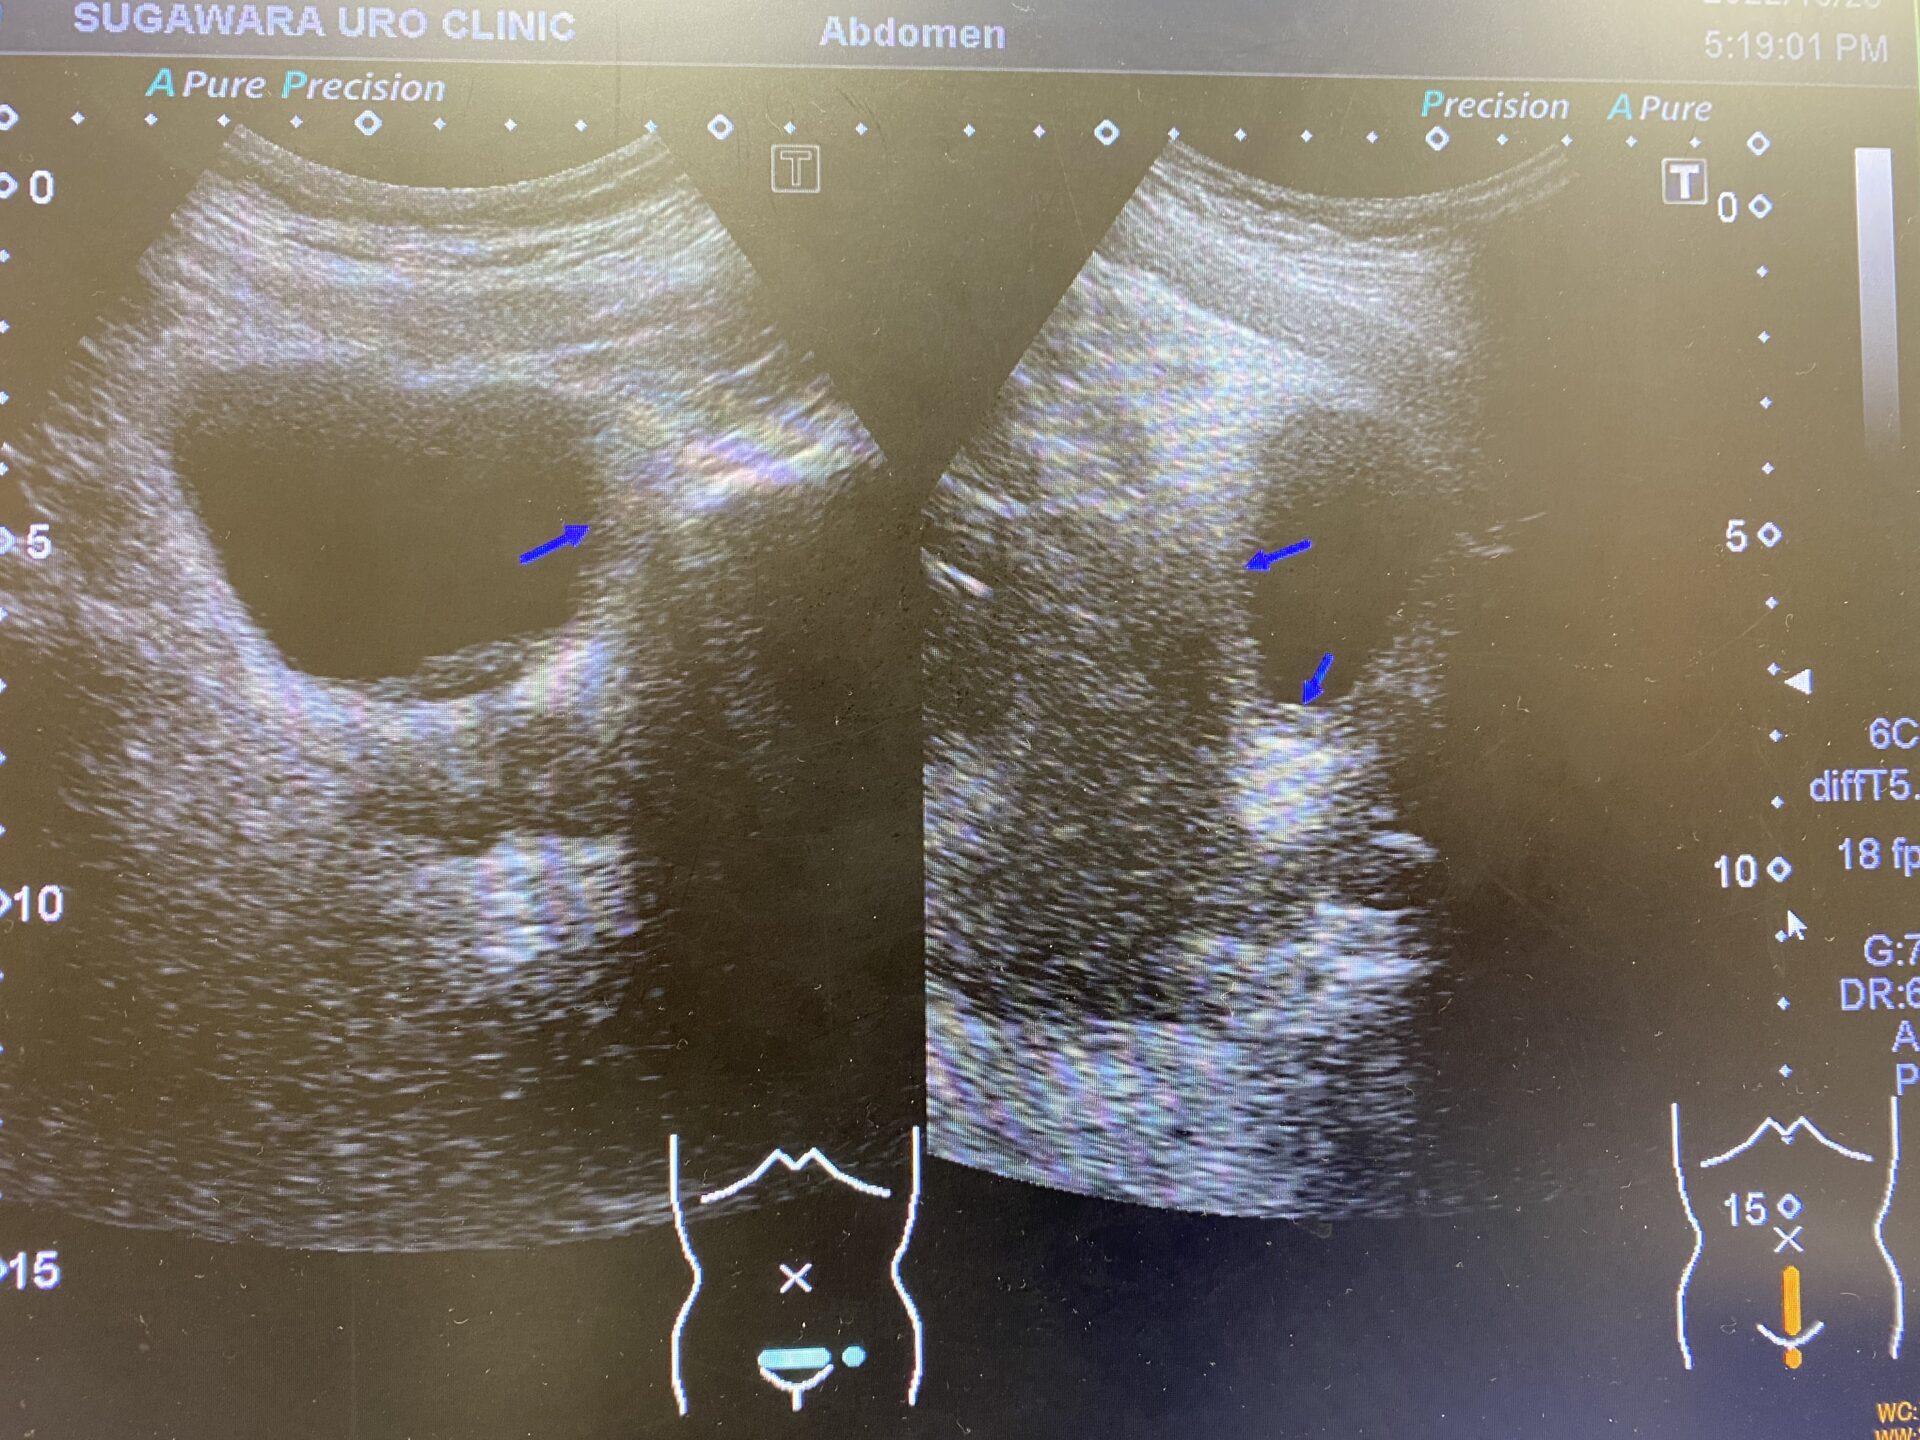

- 방광경 검사 : 방광경을 이용하여 방광 내부를 직접 관찰하고 종양의 유무를 확인합니다. 이 과정에서 조직을 채취해 생검도 진행할 수 있습니다.

- 영상 검사 : CT, MRI 등을 통해 종양의 크기와 전이 여부를 검사합니다.